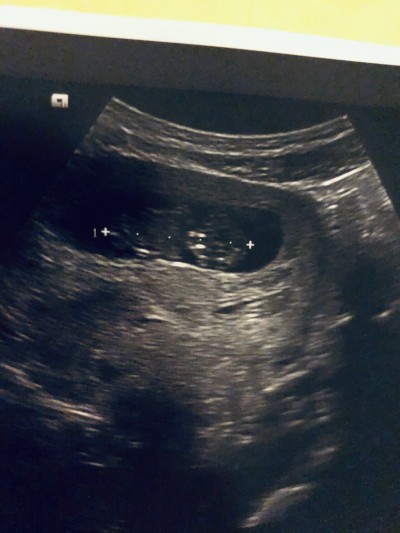

ŞŞimdiden teşekkür ederim ilk bebek olduğu için çok heyecanlıyım

Evet daha baya küçük on bir haftalık ama işte ilk heyecanla öyle sabırsızım ki

Benim 11 haftalıkken doktor tahminini söylemişti birşey demedi mi

Yurtdışında yaşıyorum canım burda nerdeyse on altı haftalık olana kadar net bişey söylemezlermiş görüp tahmin etseler bile

Aslında en başından beri erkek diye hissediyorum ama bunu cinsiyetçilikten değil içime hep öyle geçtiği için sonra da böyle deyip hata mı ediyorum diye üzülüyorum  on iki şubatta birinci trimester testleri için gidicem o zaman daha da netleşiyomuş sanırım bakalım seni dinleyip ısrar edicem inşallah derler